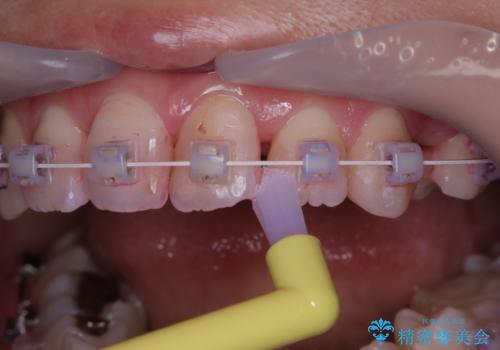

- ワイヤー矯正中のメンテナンスでPMTCを希望されました。染め出しを行い、歯ブラシ指導とPMTC30分コースを行いました。

毎日しっかりと磨いているようでも、装置の周りや歯と歯の間・歯と歯茎の間に磨き残しが残ってしまいます。そのため磨き残しをチェックする『染め出し剤』を使用すると明確に磨き残しを見ることができます。

染め出されている部分の磨き残しは、毎日の習慣として歯ブラシをしていてもいつも磨けてない部分です。

この部分をしっかりと磨けるようになると、虫歯や歯周病を予防することができます。

矯正中にも、虫歯や歯周病予防をしっかり行うことが大切です。